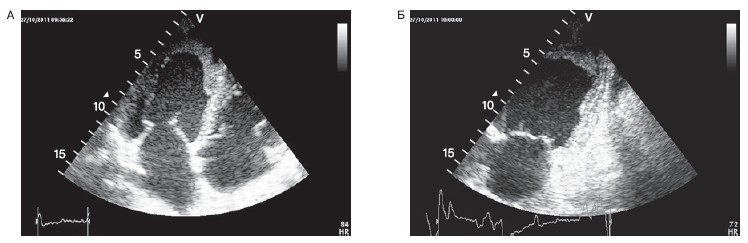

Внутрижелудочковый тромбоз. В зоне некроза миокарда и в полости аневризмы могут формироваться пристеночные тромбы. ЭхоКГ служит методом выбора для диагностики внутрижелудочковых тромбов и позволяет определить их размеры, форму, подвижность, акустическую плотность, характер контуров тромба и степень его прилежания к стенке желудочка. Чувствительность ЭхоКГ в диагностике тромбов в ЛЖ составляет 95%, а специфичность — 86% [18]. Тромбы формируются в остром периоде ИМ и всегда сопровождаются нарушениями сократимости желудочка. Внутрижелудочковые тромбы в большинстве случаев наблюдаются при передних ИМ и обычно локализуются в верхушке ЛЖ (рис. 8).

Рисунок 8. Пристеночный тромбоз верхушки левого желудочка у больного острым инфарктом миокарда.

А — верхушечный доступ, позиция 4 камер; Б — верхушечный доступ, позиция 2 камер.

Максимальная частота формирования тромбов наблюдается на 3-и сутки ИМ. Однако тромб может сформироваться и значительно раньше, особенно при обширных зонах акинезии в области верхушки сердца. Возможно формирование тромба и через несколько недель после ИМ.

При ЭхоКГ тромбы представляют собой дополнительные эхопозитивные образования, отличные от эндокарда и в разной степени проникающие в полость ЛЖ. Поверхность тромба может быть четко дифференцирована от подлежащего эндокарда и тромб может быть визуализирован минимум в двух различных позициях. Акустические характеристики острого тромбоза обычно сопоставимы с таковыми миокарда. Длительно существующие тромбы могут иметь более высокую акустическую плотность вплоть до участков кальцификации. Очень важна характеристика степени прилегания тромба к эндокарду. Иногда тромбы могут иметь центральное просветление и тогда они напоминают кисты. Однако анамнез и зоны НЛС позволяют правильно оценить данные ЭхоКГ в таких случаях.

Потенциально более опасными для возникновения тромбоэмболических осложнений являются подвижные фрагментированные тромбы с неровными контурами, неравномерной и низкой плотности, нешироко прилежащие к стенке и выступающие в просвет желудочка (рис. 9).

Рисунок 9. Эмбологенные тромбы верхушки левого желудочка у больных острым инфарктом миокарда.

А — округлый тромб нешироко прилежащий к стенке (стрелка); Б,В — тромбы с неоднородной акустической плотностью; Г — тромб с неоднородной акустической плотностью в режиме расцвечивания изображения.